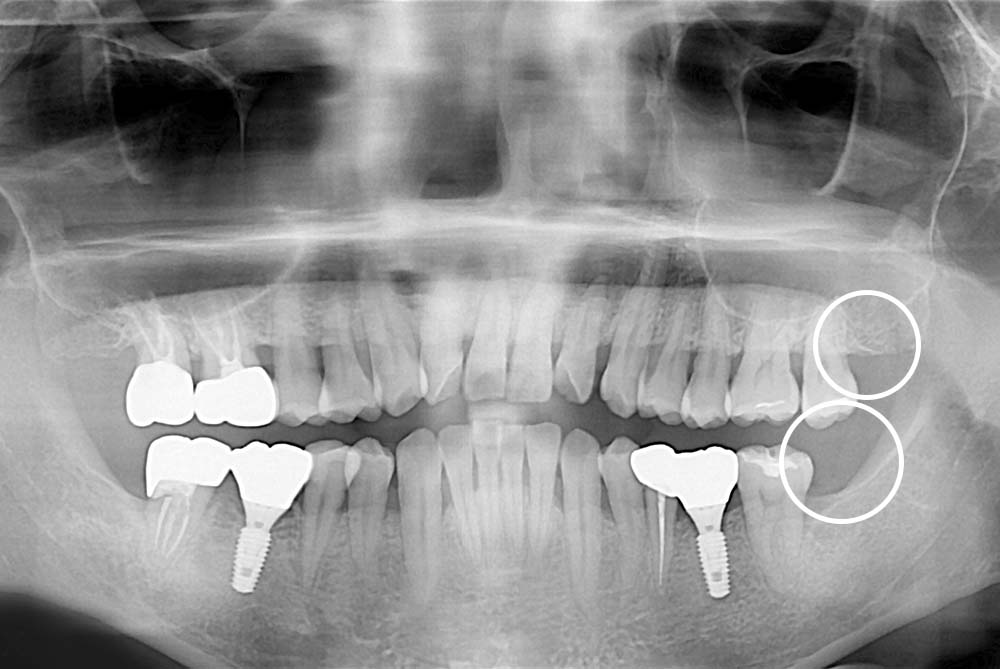

[사랑니] 매복 사랑니 발치

치료후 : 2021-02-03

세종치과는 구강악안면외과학 박사이신 원장님이 발치하는 치과입니다.